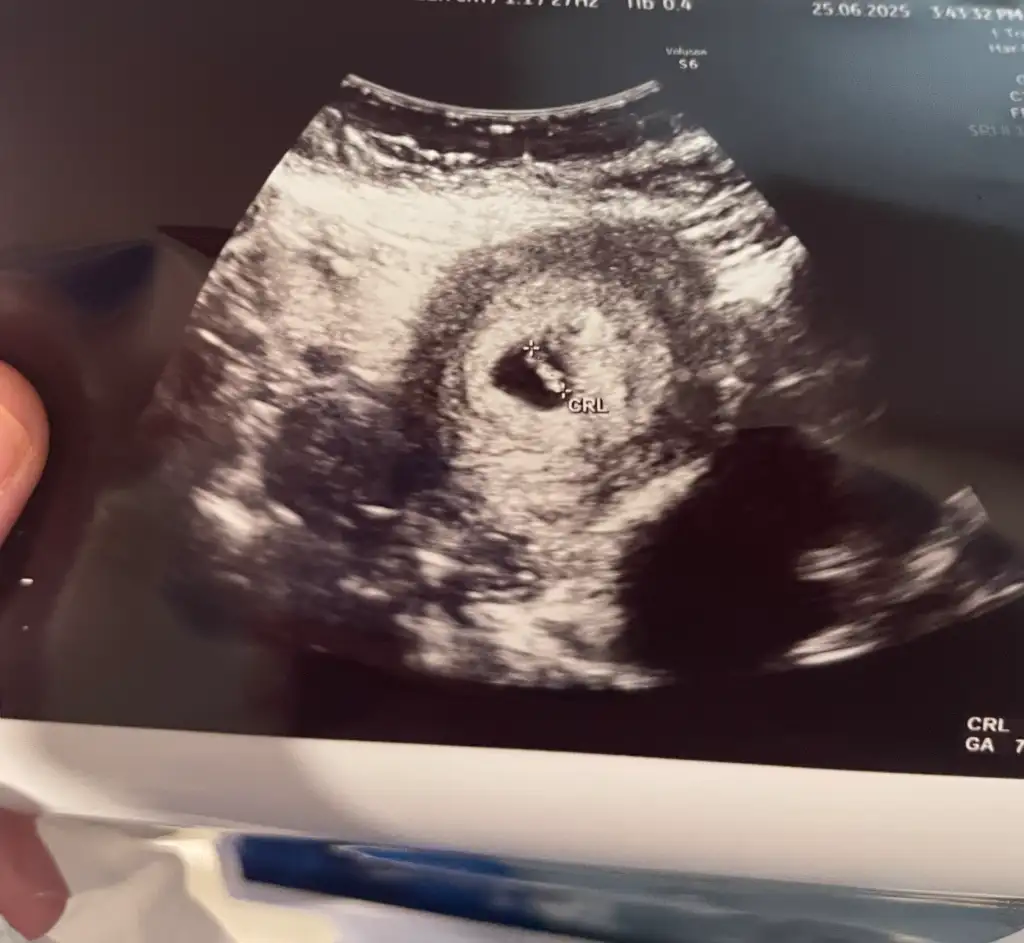

• IMG_0518.webp

IMG_0518.webp

39,2 KB · Görüntüleme: 35